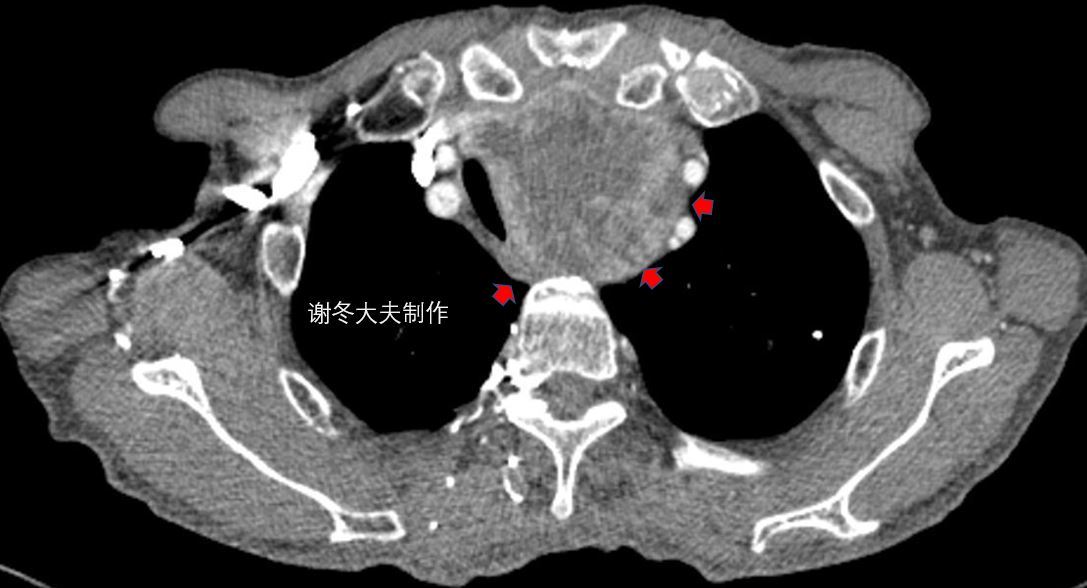

侵犯上腔静脉,伴有双侧胸水